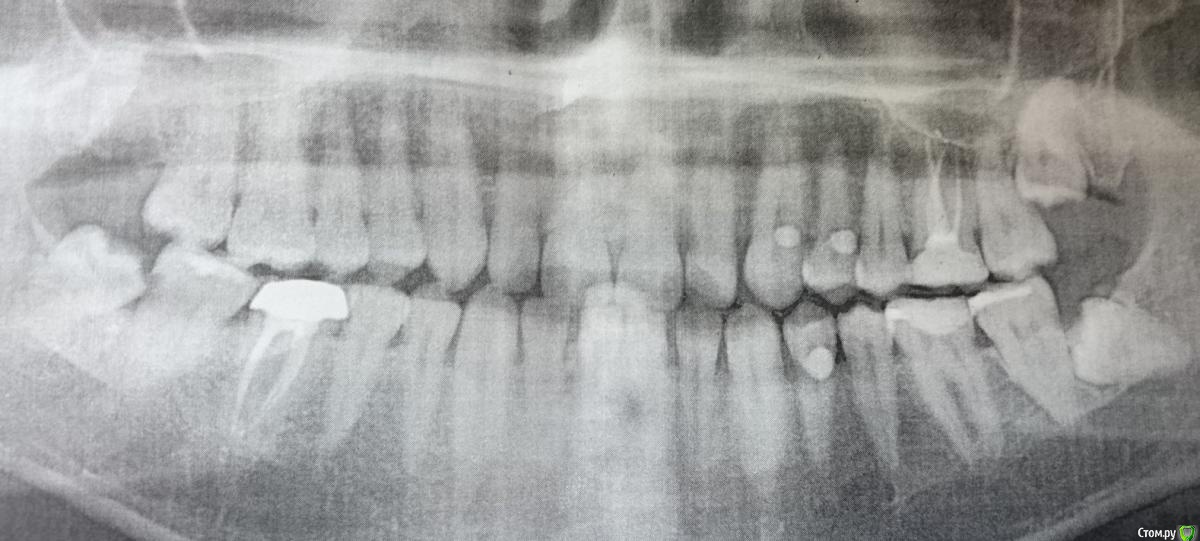

grizli81 Опубликовано 22 ноября, 2016 Автор Поделиться Опубликовано 22 ноября, 2016 Добрый день. Не стал создавать отдельную тему. Реставрацию переделали, пока ничего не болит. Также удалили все зубы мудрости и поставили пломбу на 7 зуб. Смущает наличие какого-то содержимого в лунке нижней восьмерки (удаляли уже недели 3 назад), ничего не болит, температуры нет, но лунка зарастает крайне медленно. Также смущает пломба на 7 зубе. Оцените, пожалуйста, по снимку. Ссылка на комментарий

DmitrySH Опубликовано 22 ноября, 2016 Поделиться Опубликовано 22 ноября, 2016 (изменено) Место очень проблемное для пломбы на 7. в любом случае такая пломба при таком дефекте это некий компромисс. Долговечно не сделатьНадо отполировать пломбу на 7. Изменено 22 ноября, 2016 пользователем DmitrySH Ссылка на комментарий

grizli81 Опубликовано 22 ноября, 2016 Автор Поделиться Опубликовано 22 ноября, 2016 (изменено) Т.е. пломба без дефектов и кроме полировки ничего делать не нужно? Смутила темная полоса между тканями зуба и самой пломбой + когда чистил ирригатором этот зуб обнаружил небольшой кусок цемента во рту, кроме как оттуда быть не может, т.к. все остальные пломбы абсолютно целые Изменено 22 ноября, 2016 пользователем grizli81 Ссылка на комментарий

DmitrySH Опубликовано 22 ноября, 2016 Поделиться Опубликовано 22 ноября, 2016 .е. пломба без дефектов и кроме полировки ничего делать не нужно? Смутила темная полоса между тканями зуба и самой пломбой возможно текучий неконтрастный материал. Обратитесь к своему врачу для осмотра. Ссылка на комментарий